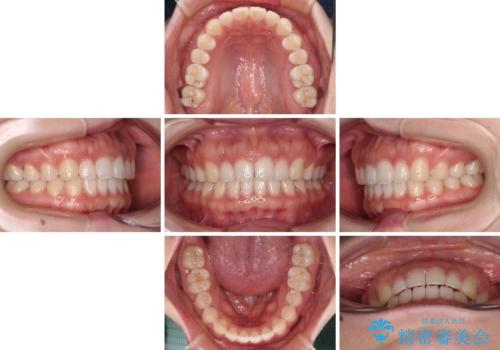

すきっ歯とオープンバイト インビザライン・ライトで改善

- 食いしばりによる顎の負担を気にして来院された患者様です。

当初は、ボツリヌス毒素による咬筋の過緊張の緩和と、睡眠時のマウスピース装着による咬合負担の解消を行いました。

オープンバイトのため、奥歯に負担のかかる咬合状態であったので、矯正治療を提案したところ、希望をされました。

すきっ歯程度の軽度の歯列不正であったため、インビザライン・ライトにより咬合改善を行うこととしました。

オープンバイトやすきっ歯は、舌突出癖によりあっという間に後戻りをするため、矯正治療前からトレーニングを行っていただき、更には後戻り防止のワイヤーリテーナーを併用しています。